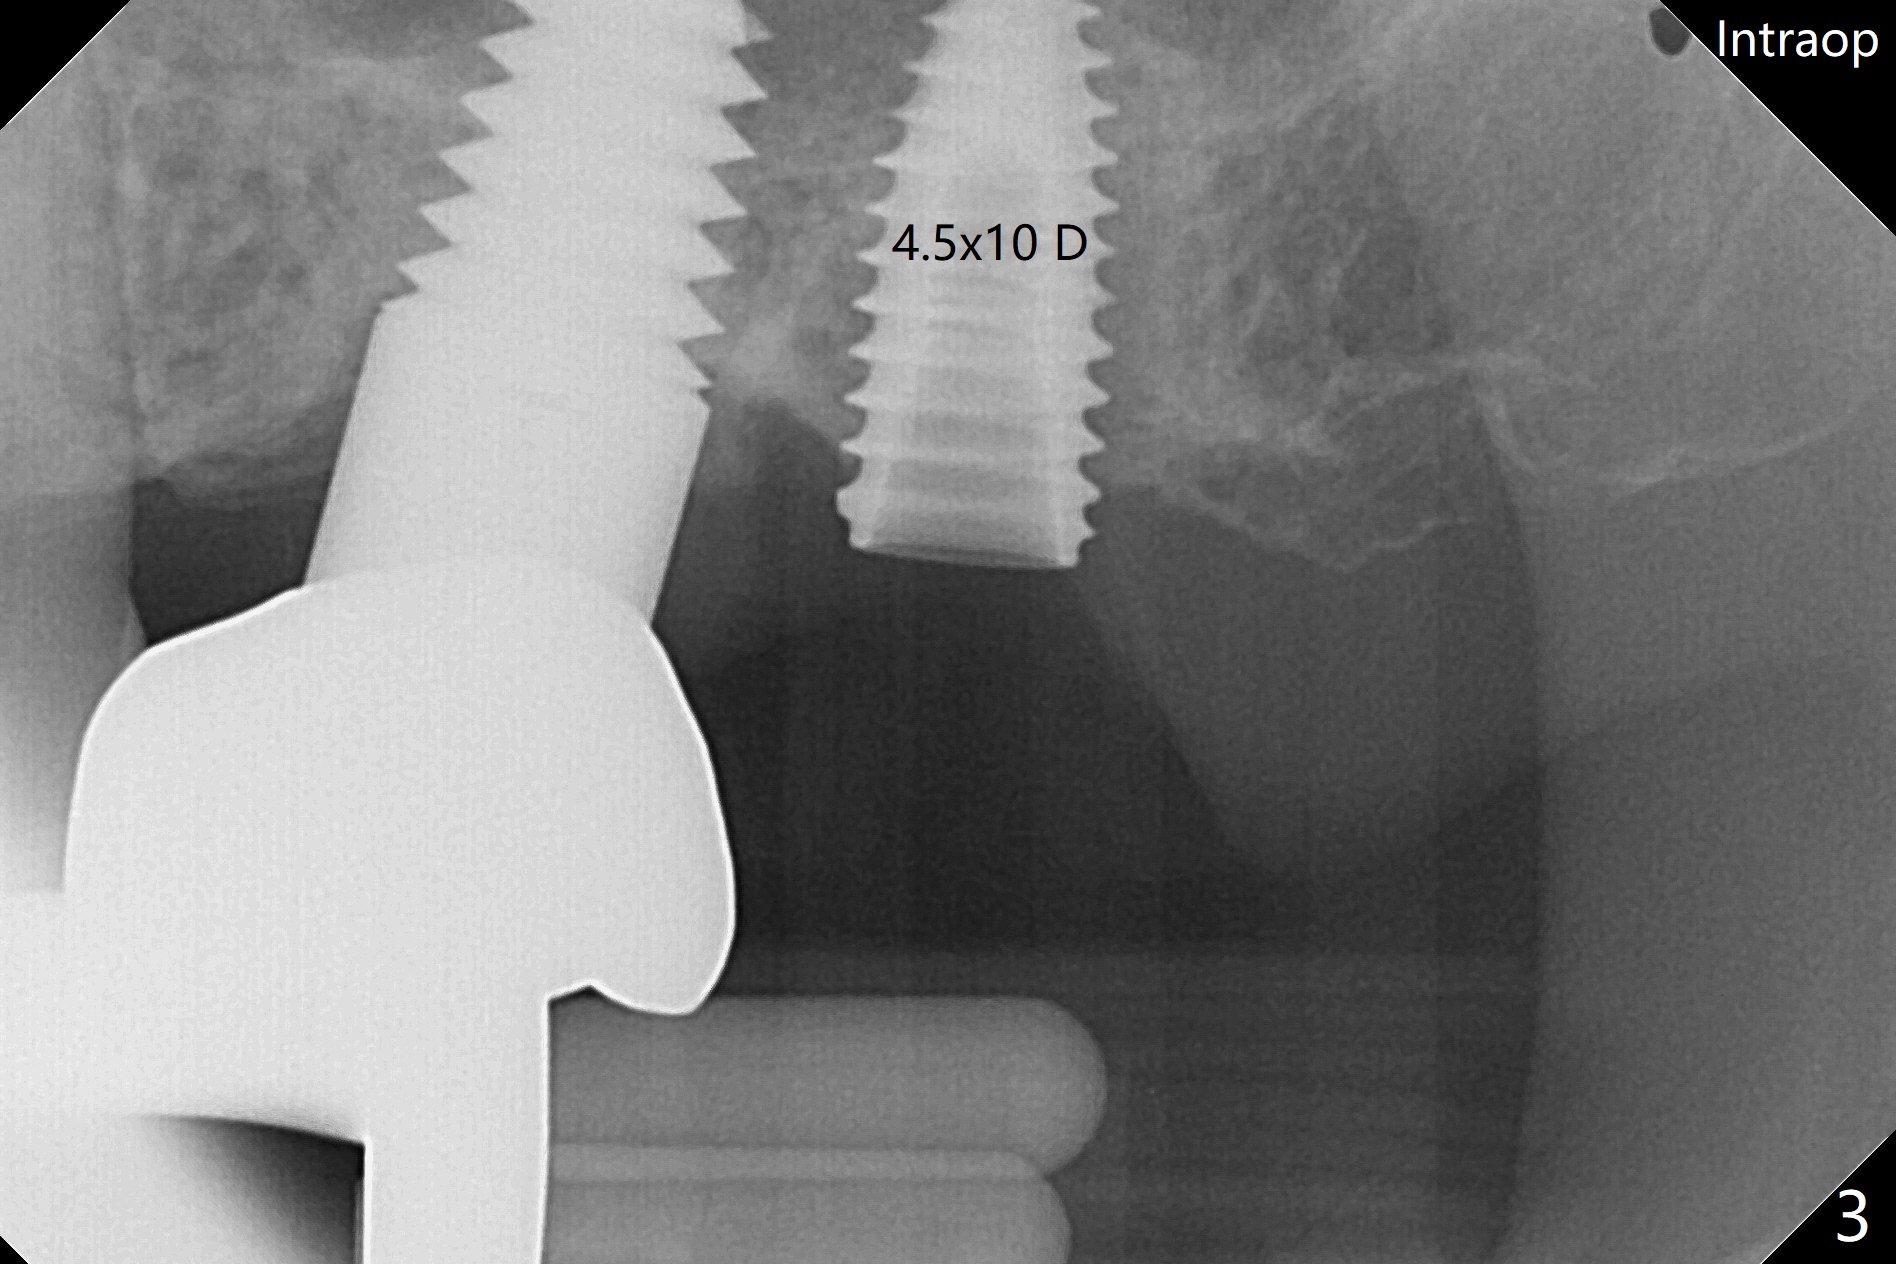

术前15号牙远中隐裂(图一:^),14号牙植体光滑面腭侧暴露(8年前腭侧窝植入),但是牙龈健康(图二)。14号牙牙槽窝没有肉芽组织,利用导板(Shinning Oral Scanner)完成3.5毫米钻洞,无法使用圆钻做内提升,改用4x10毫米报废植体提升,不幸窦膜好像破裂(因为薄),塞入半块PRF膜,促进修复,然后使用4.5x10毫米报废植体扩大植牙床(图三,四),无意达到部分提升(*),取出报废植体,发现植牙床没有穿孔了,加入少量粘性骨粉(图五:S(即使在窦内不容易分散))后,植入正式植体和基台。植体周围间隙(图五:*),使用刮匙,牙周探针,和长探针(图六)将骨粉输入深部(图七:*)。